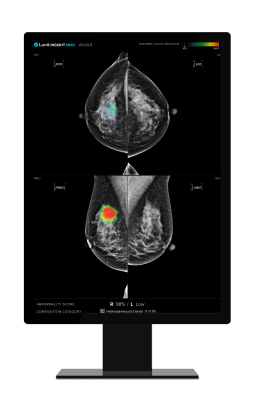

September 13, 2023 — Lunit, a leading provider of AI-powered solutions for cancer diagnostics and therapeutics, has unveiled the results of a collaborative study with Dr. Yan Chen, Ph.D., Professor of digital screening at the University of Nottingham, United Kingdom. The study, recently published in Radiology, demonstrates that Lunit's AI-powered mammography analysis solution, Lunit INSIGHT MMG, matches the diagnostic performance of human readers. The study, which involved comparing Lunit's solution with assessments by 552 human readers, represents a significant milestone in the field of medical imaging and the future of breast cancer detection.

Conducted retrospectively, the study evaluated two PERFORMS test sets, each consisting of 60 challenging cases from the NHSBSP (National Health Service Breast Screening Program), over a three-year period. Human readers assessed these cases between May 2018 and March 2021, while Lunit's AI-powered mammography analysis solution evaluated them in 2022. The AI algorithm assessed each breast individually and assigned a suspicion of malignancy score to the detected features.

In the study, no significant difference was observed in the AUC (area under the ROC curve) between Lunit's AI-powered mammography analysis solution (0.93) and human readers (0.88), demonstrating the solution's ability to excel in breast cancer detection. Additionally, when using recall thresholds to match the mean performance of human readers (90% sensitivity, 76% specificity), Lunit's AI-powered mammography analysis solution exhibited no significant differences or even stronger performance in sensitivity (91%) or specificity (77%) compared to human readers, highlighting its reliability and consistency.

In conclusion, the study demonstrates that Lunit's AI-powered mammography analysis solution performs at a level equivalent to that of an experienced radiologist when assessing cases from two enriched test sets provided by the PERFORMS scheme.